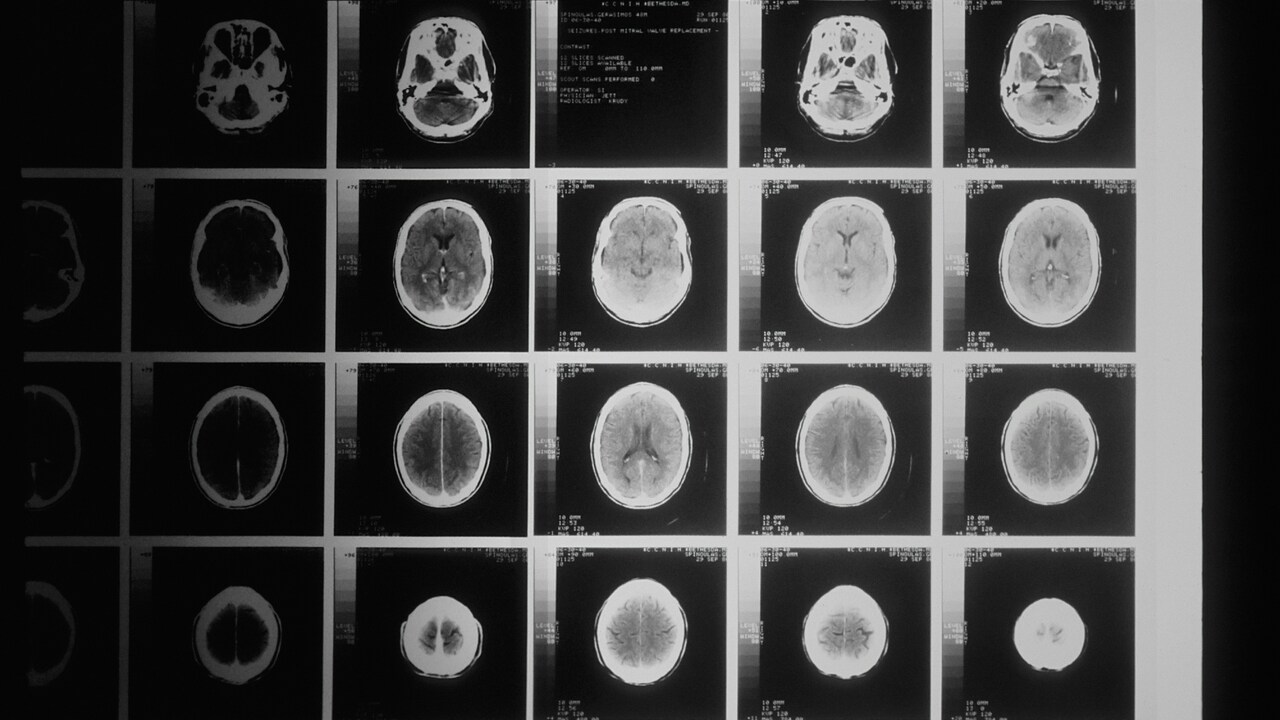

sken mozgu.jpg

Foto: Unsplash/National Cancer Institute

Súvislosť medzi používaním mobilných telefónov či ďalších podobných zariadení a nárastom výskytu rakoviny mozgu sa nepreukázala. Tvrdí to prieskum zadaný Svetovou zdravotníckou organizáciou (WHO), napísala v utorok agentúra Reuters, ktorá sa s dokumentom oboznámila.